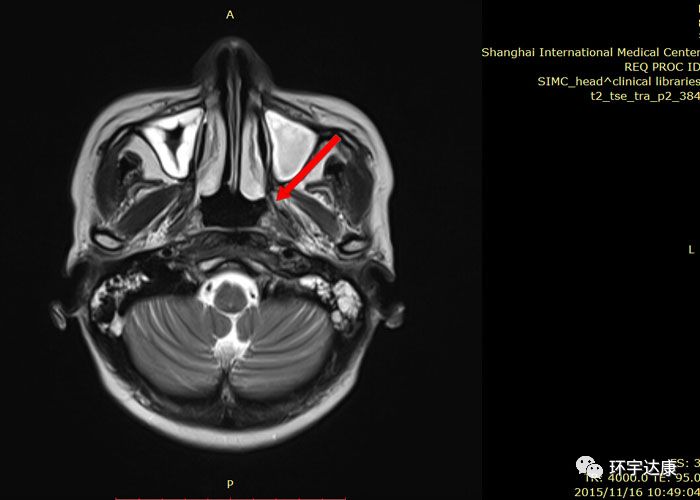

广东的吴女士在2013年7月出现左耳听力下降及左上颈明显肿大淋巴结,本以为是炎症,结果去医院检查后才被确诊为:非角化性癌,分化较差,鼻咽腔肿瘤侵润咽旁和颅底。双侧淋巴结转移。分期为:T3N1M0。

经过多西他赛+铂类化疗联合放疗后,病灶都有了明显的缩小。

不幸的是,2015年2月,复查结果显示,左侧鼻腔壁肿瘤局部复发。因为之前已经接受过了放疗,所以复发后吴女士可选的治疗方案很少。

再经过会诊后,吴女士了解到质子可以治疗复发的肿瘤,于是,吴女士选择了去国外接受质子质子治疗。

治疗期间,吴女士唾液分泌、皮肤、甲状腺无显著影响。治疗后MRI显示鼻咽左侧壁的局部复发已经明显缩小。两个月后吴女士开始正常上班。目前随访,病情处于稳定状态。